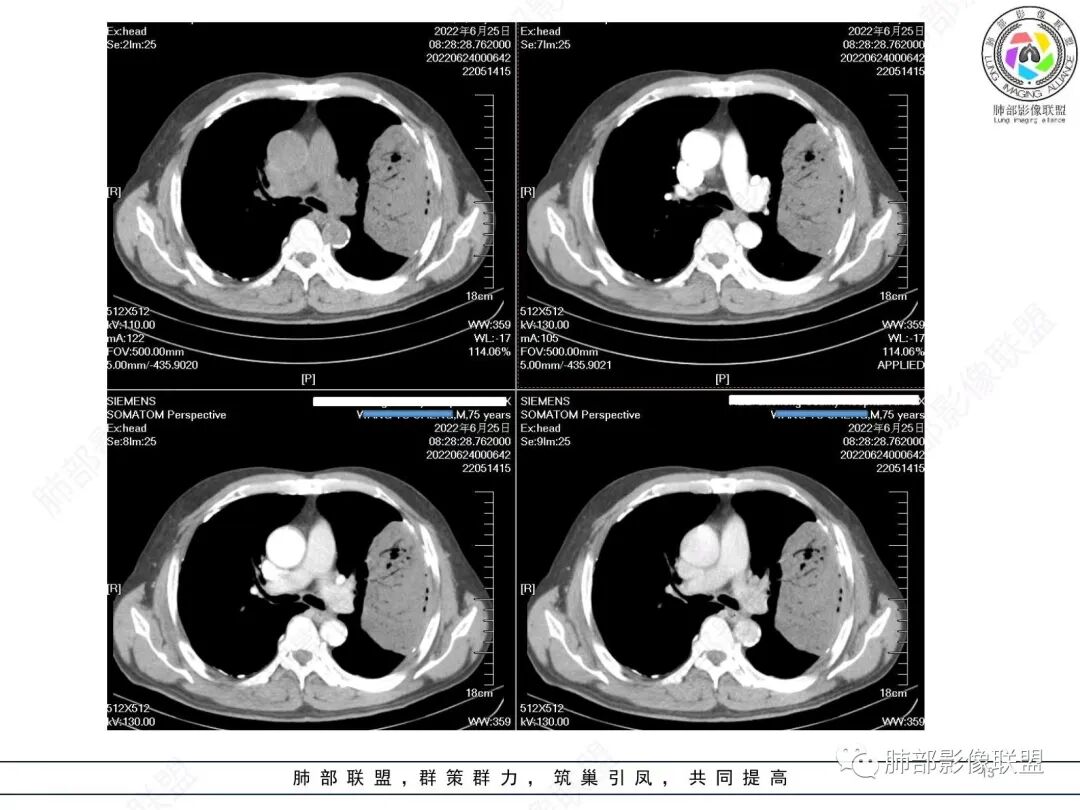

谢加平:

左肺上叶大肿块,膨胀性生长,边界清,密度较低,见部分坏死区,强化弱,肿块见支气管充气V扩张征,分布僵直,枯树枝特点,另一个重要特点血管造影征,淋巴瘤,肿块长轴与胸膜平行,与隐球菌鉴别,隐球荚膜抗原检查,明确诊断经皮肺穿刺。另胸膜钙化(问诊既往有无患胸膜炎病史)。

如果粘液腺Ca,周边太干净了,不支持。

放射小白:

老年男性左肺团块状占位,首先会考虑肉瘤/肉瘤样癌,其次大细胞肺癌,最后不排除肺结核。

飞鹰行动:

老年男性,糖尿病病史,消瘦、乏力三个月,影像表现左肺上叶胸膜下团块,有一定张力,内部疏松,可见支气管影及坏死区,增强病灶边缘环形强化,内部未见强化,考虑炎性肉芽肿病变,隐球?奴卡?放线菌?鉴别淋巴瘤。

宇宙:

左肺上叶胸膜下肿块,宽基底与胸膜相连,跨叶裂,边缘清晰膨隆,其内支气管充气,部分扩张、僵直,无明显强化,血管造影征,考虑淋巴瘤,鉴别腺癌

小兜:

左肺胸膜下巨大占位,跨叶裂,宽基底与胸膜相连,胸膜钙化,平扫密度较低,强化不明显,可见内部血管显影,支气管充气征和扩张,考虑为恶性,倾向于淋巴瘤

秦化君:

增强没有强化,血管束正常,气管束有正常有扩张,内有空洞,考虑炎性病变,隐球?

丽:

左侧胸腔巨大肿块,跨叶生长,临近胸膜钙化,边缘模糊,可见支气管影,定位肺内,增强后轻度强化,边缘见血管影,考虑淋巴瘤,鉴别肉瘤

那个人:

老年,明显消瘦,左侧胸廓轻度缩小?胸膜增厚,见钙化,以前结核?接触其他?整个肿块膨隆,坏死不明显,支气管通畅,轻度扩张轻度强化,考虑恶性,淋巴瘤可能

放射线:

左肺上叶胸膜下肿块,膨胀性生长,边界清晰,密度不均部分坏死,未见强化,病灶内支气管迂曲扩张,病灶长轴与胸膜平行,胸膜下脂肪间隙存在,胸膜钙化,考虑放线菌?毛霉?鉴别淋巴瘤

衡妈:

支持淋巴瘤,左上肺大肿块,有分叶,边缘光整,病灶内密度不均,可见支气管扩张征,增强后可见血管影征。周围肺野清晰。

赵春杨:

左肺上叶肿块,宽基底与胸膜相连,跨叶裂,边缘清晰膨隆,可见小分叶,其内支气管充气,部分扩张、僵直,呈枯枝征,支气管达边征,增强无明显强化,可见血管造影征,考虑恶性病变,淋巴瘤,鉴别粘液腺癌。

361度:

左肺团块样病灶,分叶,膨隆,不规则空洞,支气管枯枝样,血管造影征,考虑恶性,腺癌(肺肠型)。